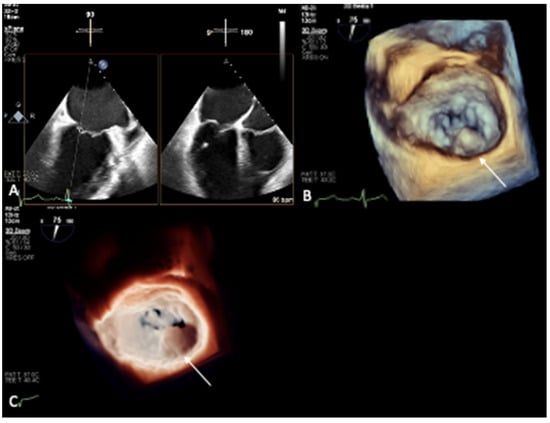

- Prandi, F.R.; Anastasius, M.O.; Zhang, L.; Tang, G.H.; Moreno, P.R.; Romeo, F.; Barillà, F.; Sharma, S.; Kini, A.; Lerakis, S. Novel Three-Dimensional Transesophageal Echocardiographic Method for Mapping Mitral Annular Calcifications. J. Am. Soc. Echocardiogr. 2022, 35, 1004–1005. [Google Scholar] [CrossRef] [PubMed]